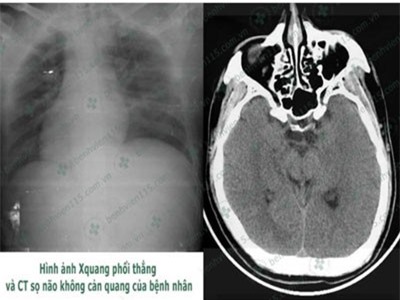

Ngày 17/12, Bệnh viện Nhân dân 115 TP.HCM vừa cấp cứu tài xế bị bệnh tiểu đường, hạ đường huyết nghiêm trọng dẫn đến hôn mê sâu do quên ăn sáng.

Lúc được đưa đến viện, nam thanh niên 25 tuổi trong tình trạng ngừng thở, ngừng tim, đồng tử hai bên giãn tối đa, không phản xạ với ánh sáng. Sau 6 lần cấp cứu, sốc điện, tim của bệnh nhân đã đập trở lại. Đây là ca bệnh tim ngừng đập lâu nhất được cứu sống tại viện.